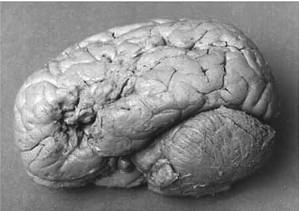

图1 Broca语言区

患者Leborgne脑左侧(自Dronkers等,2007)